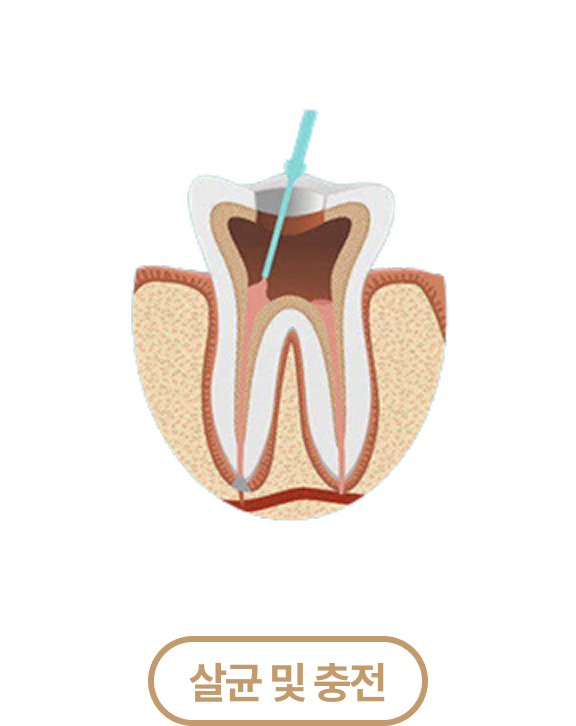

신경치료 치료과정

신경치료 PROCESS

치아 겉면의 충치와 염증이 발생한

내부 신경조직 제거

치아 뿌리 내부에

멸균 재료를 넣어 충전